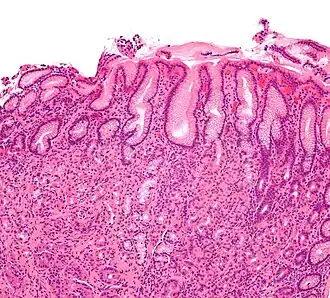

Une gastrite est une maladie inflammatoire de la paroi de l'estomac.

Le diagnostic positif de la gastrite est anatomopathologique.

La gastrite peut se diagnostiquer grâce à la clinique ou par endoscopie des voies digestives (gastroscopie). Les diagnostics différentiels sont l'ulcère gastro-duodénal et le cancer de l'estomac.